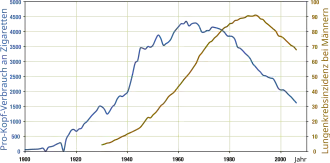

Lung cancer is the most diagnosed and deadliest cancer worldwide, with 2.2 million cases in 2020 resulting in 1.8 million deaths.[4] Lung cancer is rare in those younger than 40; the average age at diagnosis is 70 years, and the average age at death 72.[3] Incidence and outcomes vary widely across the world, depending on patterns of tobacco use. Prior to the advent of cigarette smoking in the 20th century, lung cancer was a rare disease. In the 1950s and 1960s, increasing evidence linked lung cancer and tobacco use, culminating in declarations by most large national health bodies discouraging tobacco use.

Tobacco smoking is by far the major contributor to lung cancer, causing 80% to 90% of cases.[66] Lung cancer risk increases with quantity of cigarettes consumed.[67] Tobacco smoking's carcinogenic effect is due to various chemicals in tobacco smoke that cause DNA mutations, increasing the chance of cells becoming cancerous.[68] The International Agency for Research on Cancer identifies at least 50 chemicals in tobacco smoke as carcinogenic, and the most potent is tobacco-specific nitrosamines.[67] Exposure to these chemicals causes several kinds of DNA damage: DNA adducts, oxidative stress, and breaks in the DNA strands.[69] Being around tobacco smoke – called passive smoking – can also cause lung cancer. Living with a tobacco smoker increases one's risk of developing lung cancer by 24%. An estimated 17% of lung cancer cases in those who do not smoke are caused by high levels of environmental tobacco smoke.[70]

History

Lung cancer was uncommon before the advent of cigarette smoking. Surgeon Alton Ochsner recalled that as a Washington University medical student in 1919, his entire medical school class was summoned to witness an autopsy of a man who had died from lung cancer, and told they may never see such a case again.[101][102] In Isaac Adler's 1912 Primary Malignant Growths of the Lungs and Bronchi, he called lung cancer "among the rarest forms of disease";[103] Adler tabulated the 374 cases of lung cancer that had been published to that time, concluding the disease was increasing in incidence.[104] By the 1920s, several theories had been put forward linking the increase in lung cancer to various chemical exposures that had increased including tobacco smoke, asphalt dust, industrial air pollution, and poisonous gasses from World War I.[104]

Over the following decades, growing scientific evidence linked lung cancer to cigarette consumption. Through the 1940s and early 1950s, several case-control studies showed that those with lung cancer were more likely to have smoked cigarettes compared to those without lung cancer.[105] These were followed by several prospective cohort studies in the 1950s – including the first report of the British Doctors Study in 1954 – all of which showed that those who smoked tobacco were at dramatically increased risk of developing lung cancer.[105]